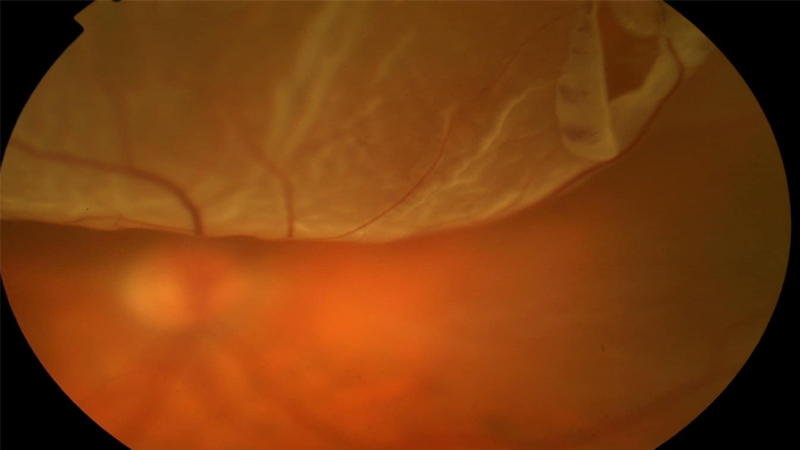

Retinal detachment is a serious eye condition in which the retina—the light-sensitive tissue at the back of the eye—pulls away from its normal position. This separation prevents the retina from functioning properly and can cause permanent vision loss if not treated promptly. Warning signs include sudden flashes of light, a sudden increase in floaters, or the appearance of a dark curtain or shadow moving across your vision. Retinal detachment is a medical emergency that requires immediate attention. At Dr. Praveen Eye Hospital and Research Centre, we use advanced diagnostic tools and surgical techniques to reattach the retina and preserve as much vision as possible, offering urgent and specialized care for this sight-threatening condition.